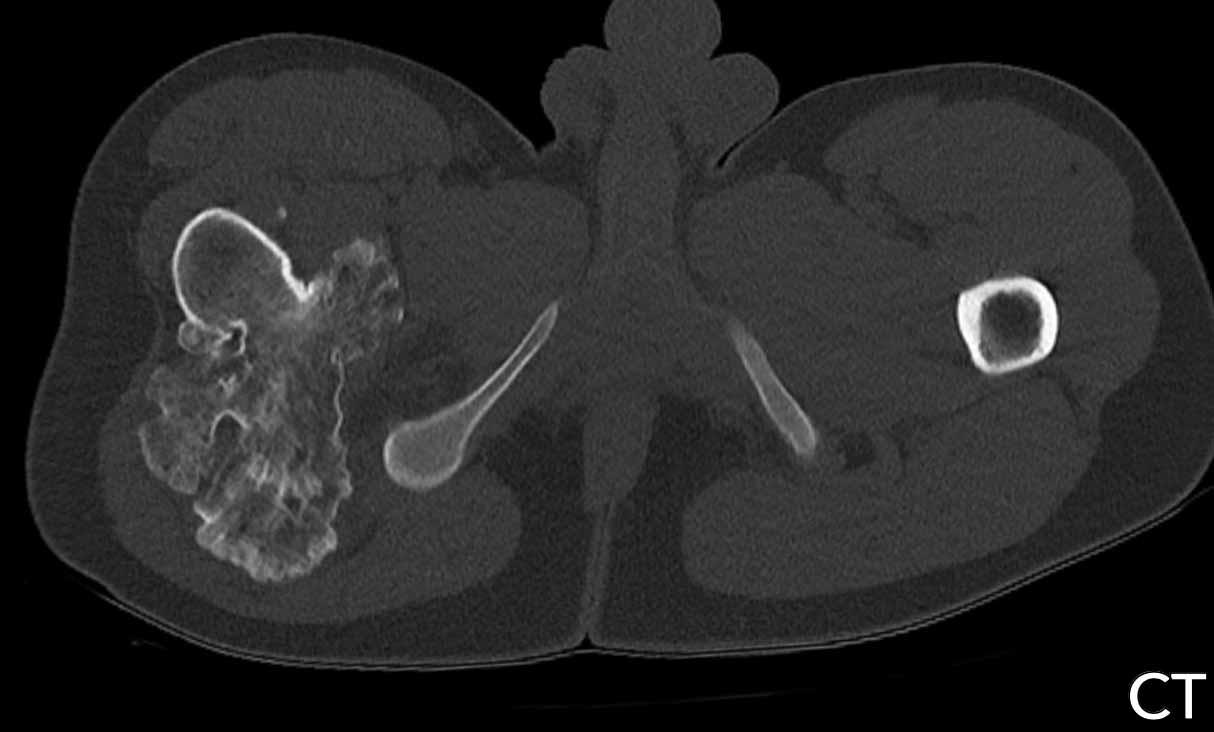

Hình ảnh

Phim X-quang cho thấy một khối u lớn ở thân xương đùi với hình ảnh vôi hóa dạng bỏng ngô điển hình ở phần xa và thành phần tiêu xương nhiều hơn ở phần gần.

Hình ảnh phóng đại chi tiết ở tư thế nghiêng cho thấy khối u xâm lấn vỏ xương và nguy cơ cao gãy xương bệnh lý.

Phần đuôi của khối u có hình ảnh giống u sụn không điển hình (ACT) với hiện tượng lõm vỏ xương khu trú, trong khi phần đầu có hình ảnh giống u sụn ác tính độ cao (CS độ cao).

Kết luận

Đây là hình ảnh điển hình của sarcoma sụn phản biệt hóa, với một phần có biểu hiện như khối u sụn độ thấp đến trung bình với sự chuyển tiếp đột ngột sang thành phần sarcoma độ cao (đôi khi không có nguồn gốc sụn).

Phân nhóm này

thường gặp ở người lớn tuổi.

Tỷ lệ sống còn toàn bộ của sarcoma sụn phân hóa kém rất thấp so với sarcoma sụn độ II và độ III, do bệnh nhân thường đã có di căn phổi và xương tại thời điểm chẩn đoán.

Lưu ý khuyết tật vỏ xương trên ảnh T2 DIXON axial và khối mô mềm xung quanh.

Một phần khối u không ngấm thuốc và vùng chất nhầy này cho thấy đây là u sụn ác tính độ cao.

Như trên phim X-quang, trường hợp này là một chondrosarcoma phân hóa kém điển hình, trong đó phần dưới có biểu hiện như một ACT và phần gần như một sarcoma độ cao.

Thường gặp dưới dạng khối u lớn ở bệnh nhân cao tuổi.